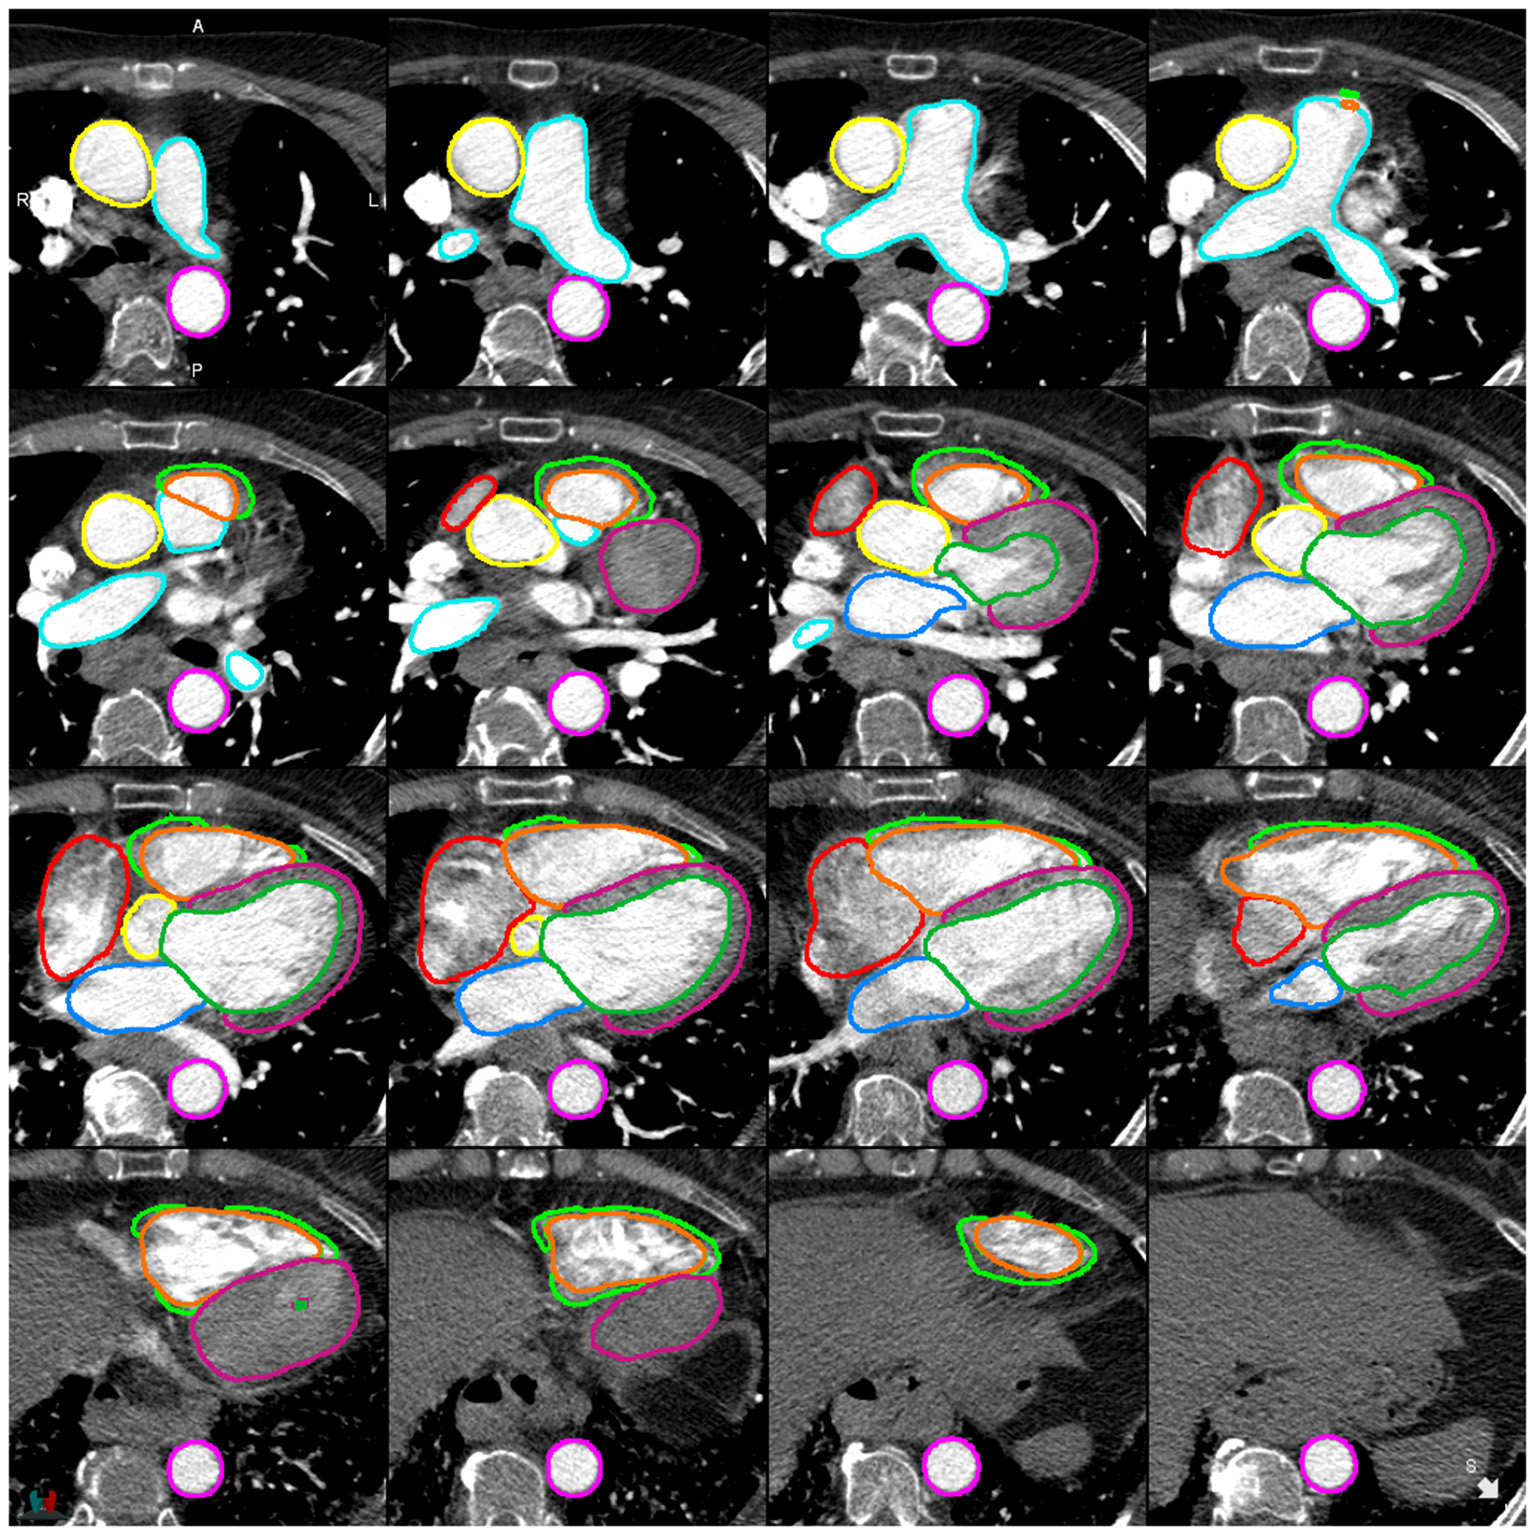

Evaluation of DL-1 and DL-2 in the test cohort (n = 100) (see Figure 3; Table 4; Supplementary Figure C) demonstrated that the additional fifty training cases used for training DL-2 improved the overall performance of the segmentation. DSC performance was similar for both models in the external cohort, with it being too small a sample (n = 20) to reach statistically significant conclusions. Bland-Altman plots for DSC in the test cohort and evaluation cohort are available in the Supplementary Figures D,E. Examples of successful DL-2 segmentation in a suspected PH patients can be found in Figures 4, 5 and Supplementary Videos A (axial) and B (sagittal). The NSD scores in the internal test cohort is marginally improved in DL-2 compared to DL-1 (Table 4).

Figure 4

Example of a successful segmentation by DL-2 for a patient with suspected PH in the internal test cohort.

Figure 5

Example of a successful segmentation by DL-2 for a patient with suspected PH in the external test cohort.